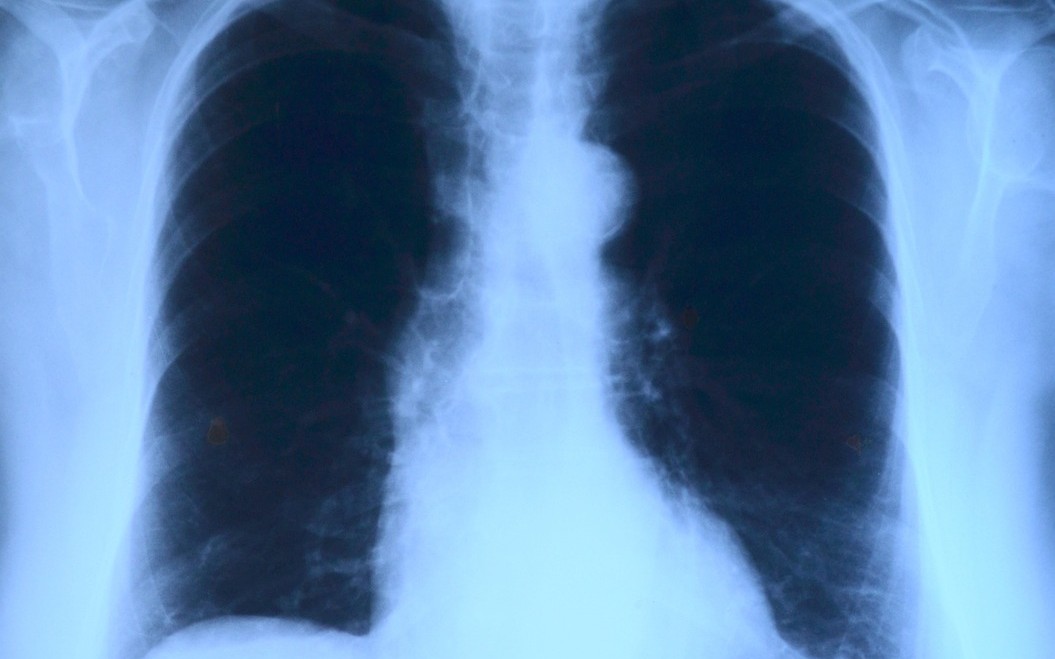

Co se týče již zmiňované plicní ambulance v budově polikliniky Nemocnice Most, ústecký lékař Viacheslav Shemota zde bude ordinovat od pondělí do čtvrtka, v pátek bude pacientům k dispozici jen zdravotní sestra. „Reference na tohoto odborníka jsou skvělé. Za poskytnuté finance chce pořídit nové speciální vybavení, které mu urychlí diagnostiku a bude se tak moci věnovat více pacientům," doplnila Markéta Stará.